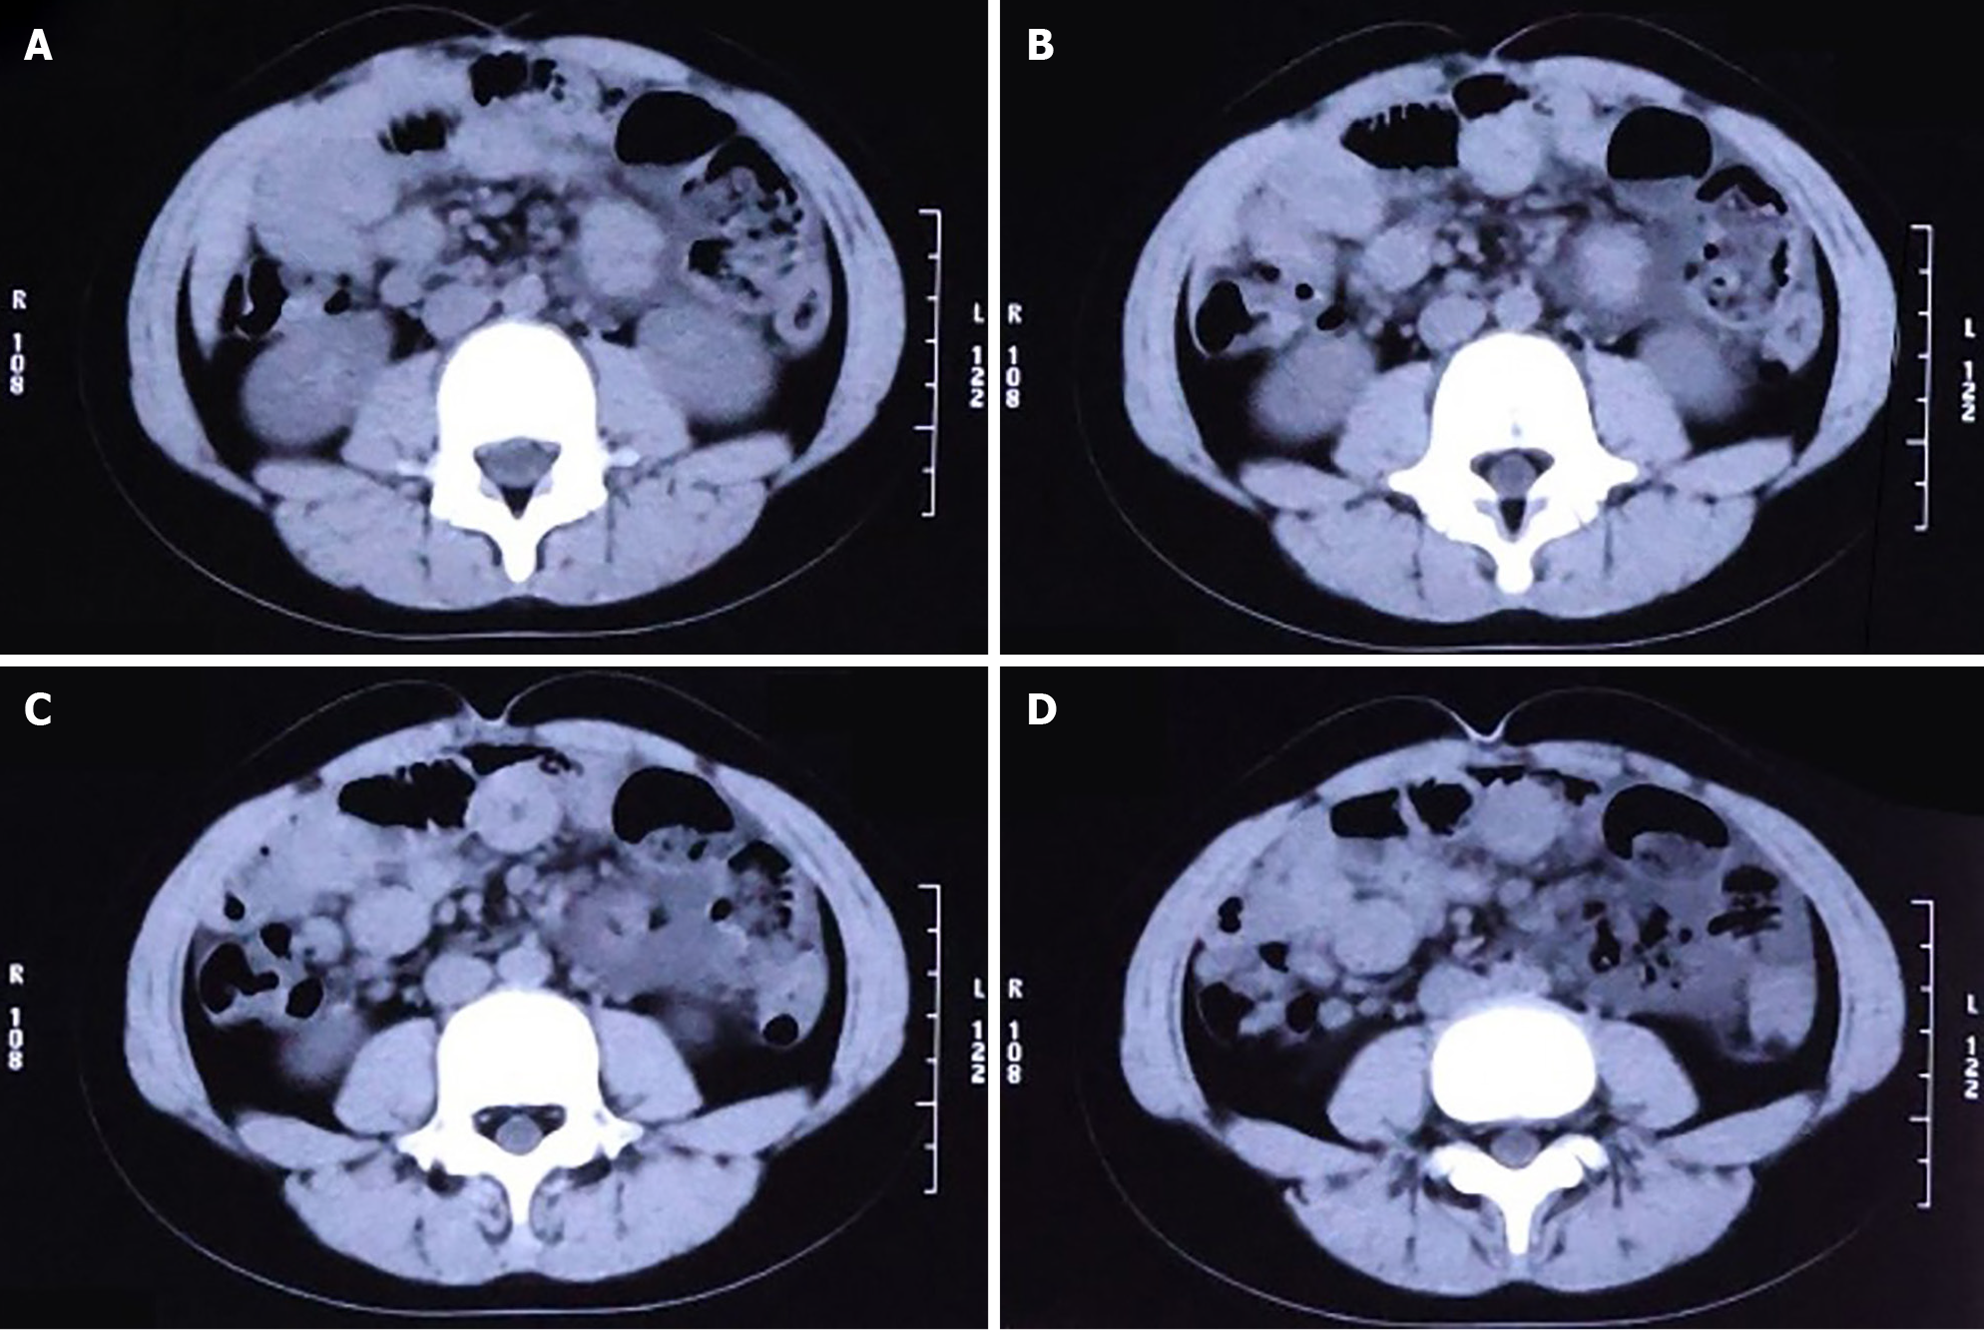

Because emergency examinations suggested signs of acute intestinal obstruction, the child was transferred to the Pediatric Surgery Department for further treatment. We proceeded with an abdominal computed tomography (CT) scan, the results of which were consistent with changes indicative of intestinal obstruction: (1) The intestinal tract within the abdominal cavity was disorganized, with a significant number of air-fluid levels visible (Figure 2A); (2) The obstruction point was located below and to the left of the umbilicus; the proximal small intestine was situated in the pelvic cavity and contained a large amount of intestinal content (Figure 2B); (3) The intestinal wall at the point of obstruction was markedly thickened, with pronounced exudation from the surrounding intestinal tract (Figure 2C); (4) The colon and rectum were collapsed (Figure 2D); and (5) Soft tissue structures were observed surrounding the small intestine, enveloping it and exhibiting a distinctive "accordion-like" appearance (Figure 3A and B).